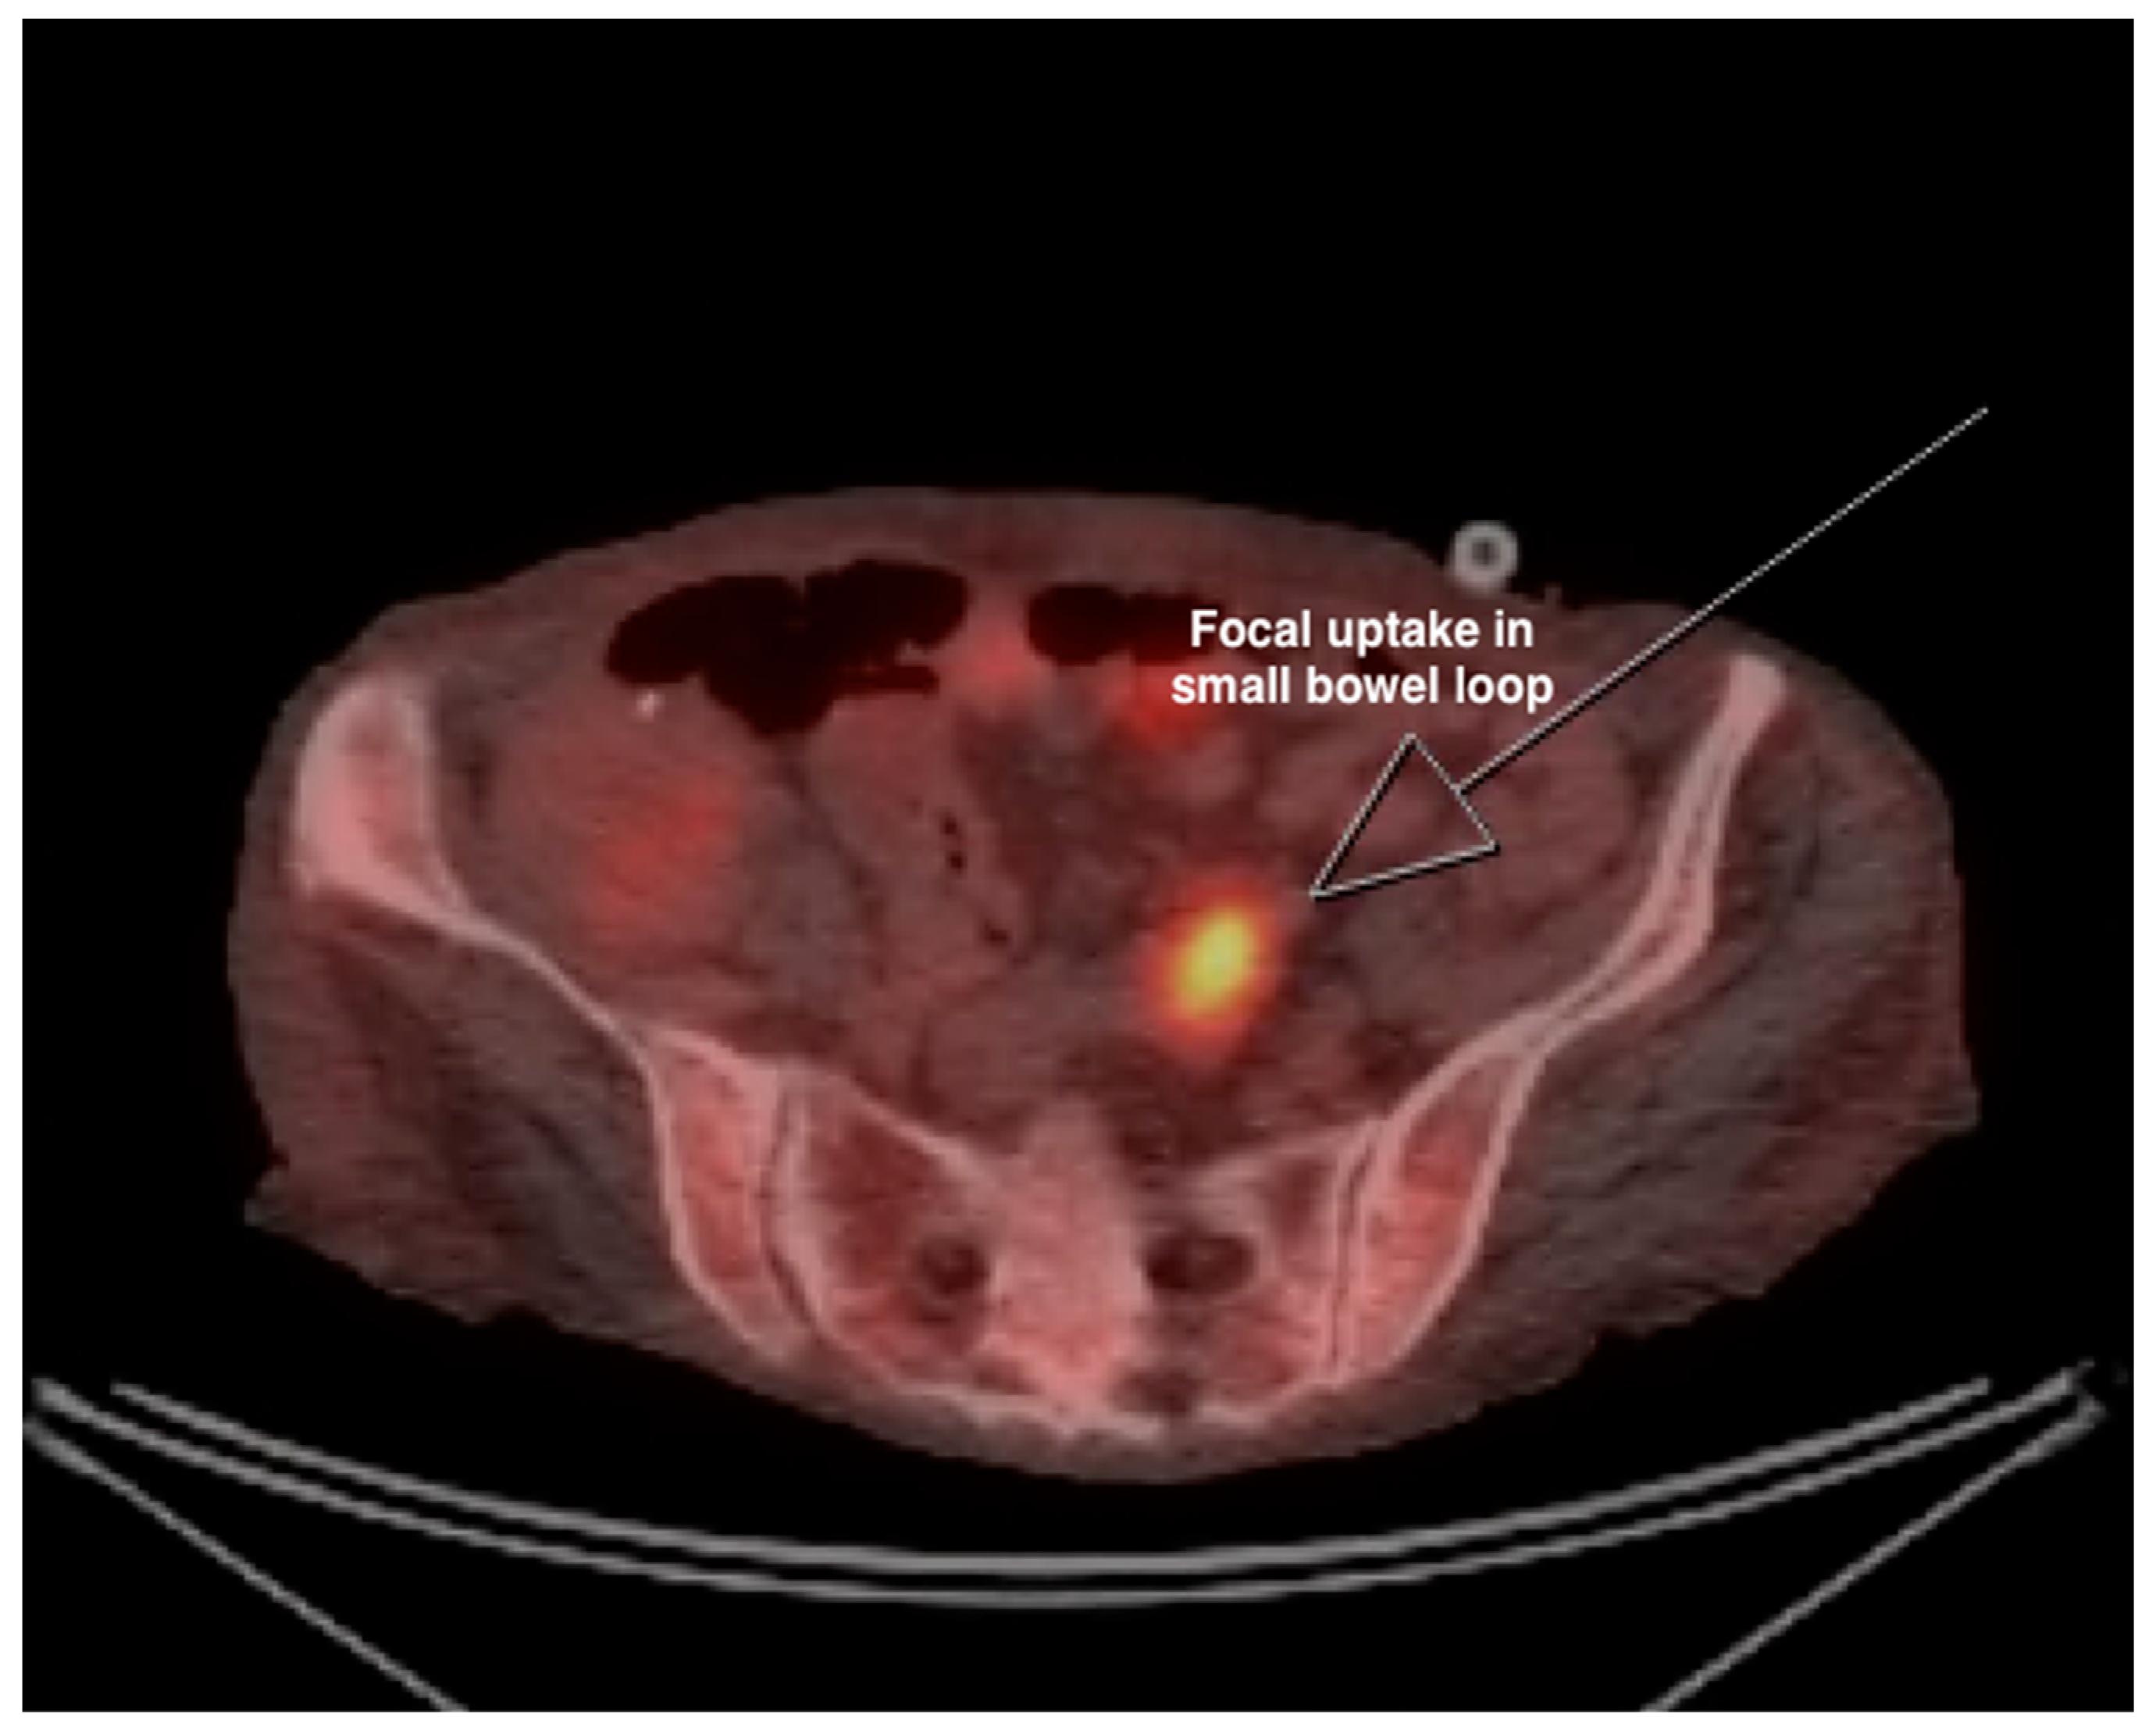

| 10 | PET-CT (Figure 2 and Figure 3) | Focal intense FDG uptake in the left upper quadrant in the small bowel loop and multifocal FDG avid hepatic metastasis. |